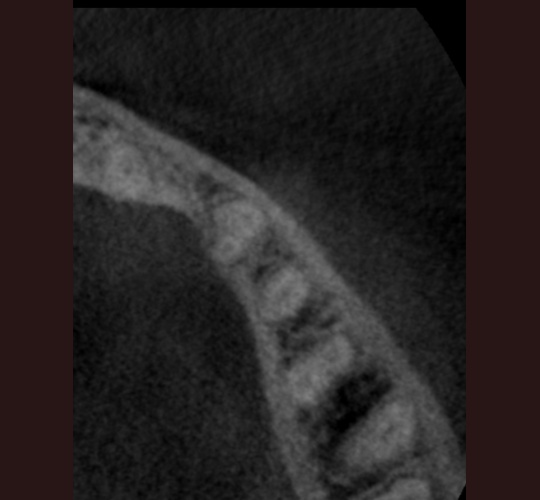

CBCT Diagnosis: Case #3

The CBCT (Cone Beam Computed Tomography) was instrumental in identifying multiple canals in this tooth. We knew from the conventional 2 dimensional radiograph that there were at least 2 roots/canals present. The CBCT showed 3 canals present. I was able to get access in all three canals and seal them.